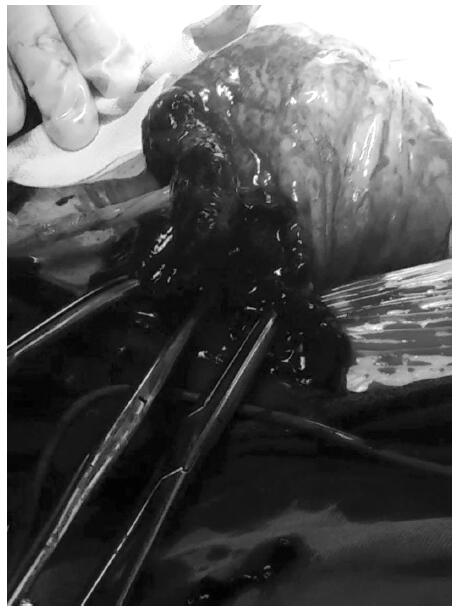

A 28-year-old woman arrived at the emergency department presenting 19 weeks of amenorrhea with severe abdominal pain for two hours. She complained of lower right abdominal pain progressed during the last two weeks; she also mentioned dizziness, but denied syncopy. She had a previous history of an abortion. The heart rate was 120 beats per minute, blood pressure was 111/76 mmHg, and temperature was 37.4°C. Her abdomen presented a generalized tenderness, guarding, rigidity, and rebound tenderness, and no vaginal bleeding was observed. Emergency bedside ultrasonography revealed intrauterine gestation without detectable fetal heart pulsation and moderate amount of free fluids in the Douglas cul-de-sac. Non-clotting blood was obtained from transabdominal puncture. Furthermore, an emergency abdominal and pelvic non-enhanced CT scan was performed and demonstrated an empty uterine cavity bent left laterally and compressed by an amniotic sac adjacent to the right cornal region of the uterus (Figure 1). Her hemoglobin level was 7.4 g/L. During laparotomy, it was observed that the right uterine angle was enlarged by approximately 20 cm, as well as cystic gestational swelling, which was displacing the reflection of the round ligament laterally. Partial surface of the swelling with active bleeding appeared black and fragile, and uncovered with myometrium. Placenta located at the right uterine horn, firmly attached to the uterine wall and extended through the entire myometrial layer (Figure 2). Placenta histopathology also confirmed placenta percreta subsequently. Both ovaries and fallopian tubes were normal. As the patient was with no offspring, partial cornuectomy and uterine reconstruction was performed for fertility preservation after discussion with the family about rupture risk for the subsequent pregnancy. The postoperative course was uneventful and the patient was discharged on postoperative day 8. No complications were detected during the follow-up period.

Figure 2.— Placenta at the right uterine horn, firmly attached to the uterine wall and extended through the entire myometrial layer